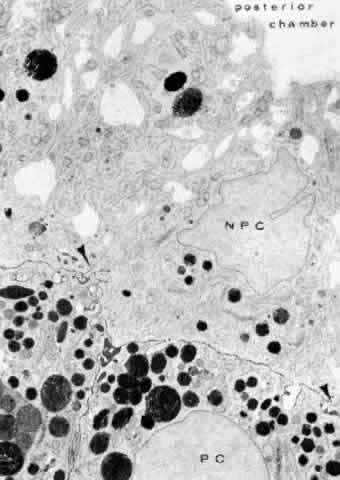

There are a large number of intercellular junctions between the ciliary epithelial cells, each giving important data about the specific functions of these cells (see Fig. 11). Toward the base of the NPE cells their lateral sides are joined by desmosomes (see Fig. 15). At their apical ends they are connected by typical tight junctional complexes consisting of a zonula occludens and zonula adherens (Fig. 19). These tight junctions represent the primary blood-aqueous barrier in the ciliary body. When large tracer molecules such as horseradish peroxidase are injected intravenously into primates,20,21 the tracer has an easy passage through the fenestrated capillaries of the ciliary processes, but does not pass beyond the apices of the NPE cells (see Fig. 19).

Fig. 19. Evidence of tight junctional complexes in the anterior ciliary epithelium of Macaca mulatta. The pigmented epithelial cells (PC) are outlined by a thin black line that is the reaction product of horeseradish peroxidase, a tracer substance injected intravenously in vivo. The tracer has entered the intercellular spaces of the nonpigmented epithelium (NPC) but is held up by occluding junctions (arrowheads), preventing further progress into the posterior chamber. (X 8450; Courtesy of Dr. Guiseppina Raviola)